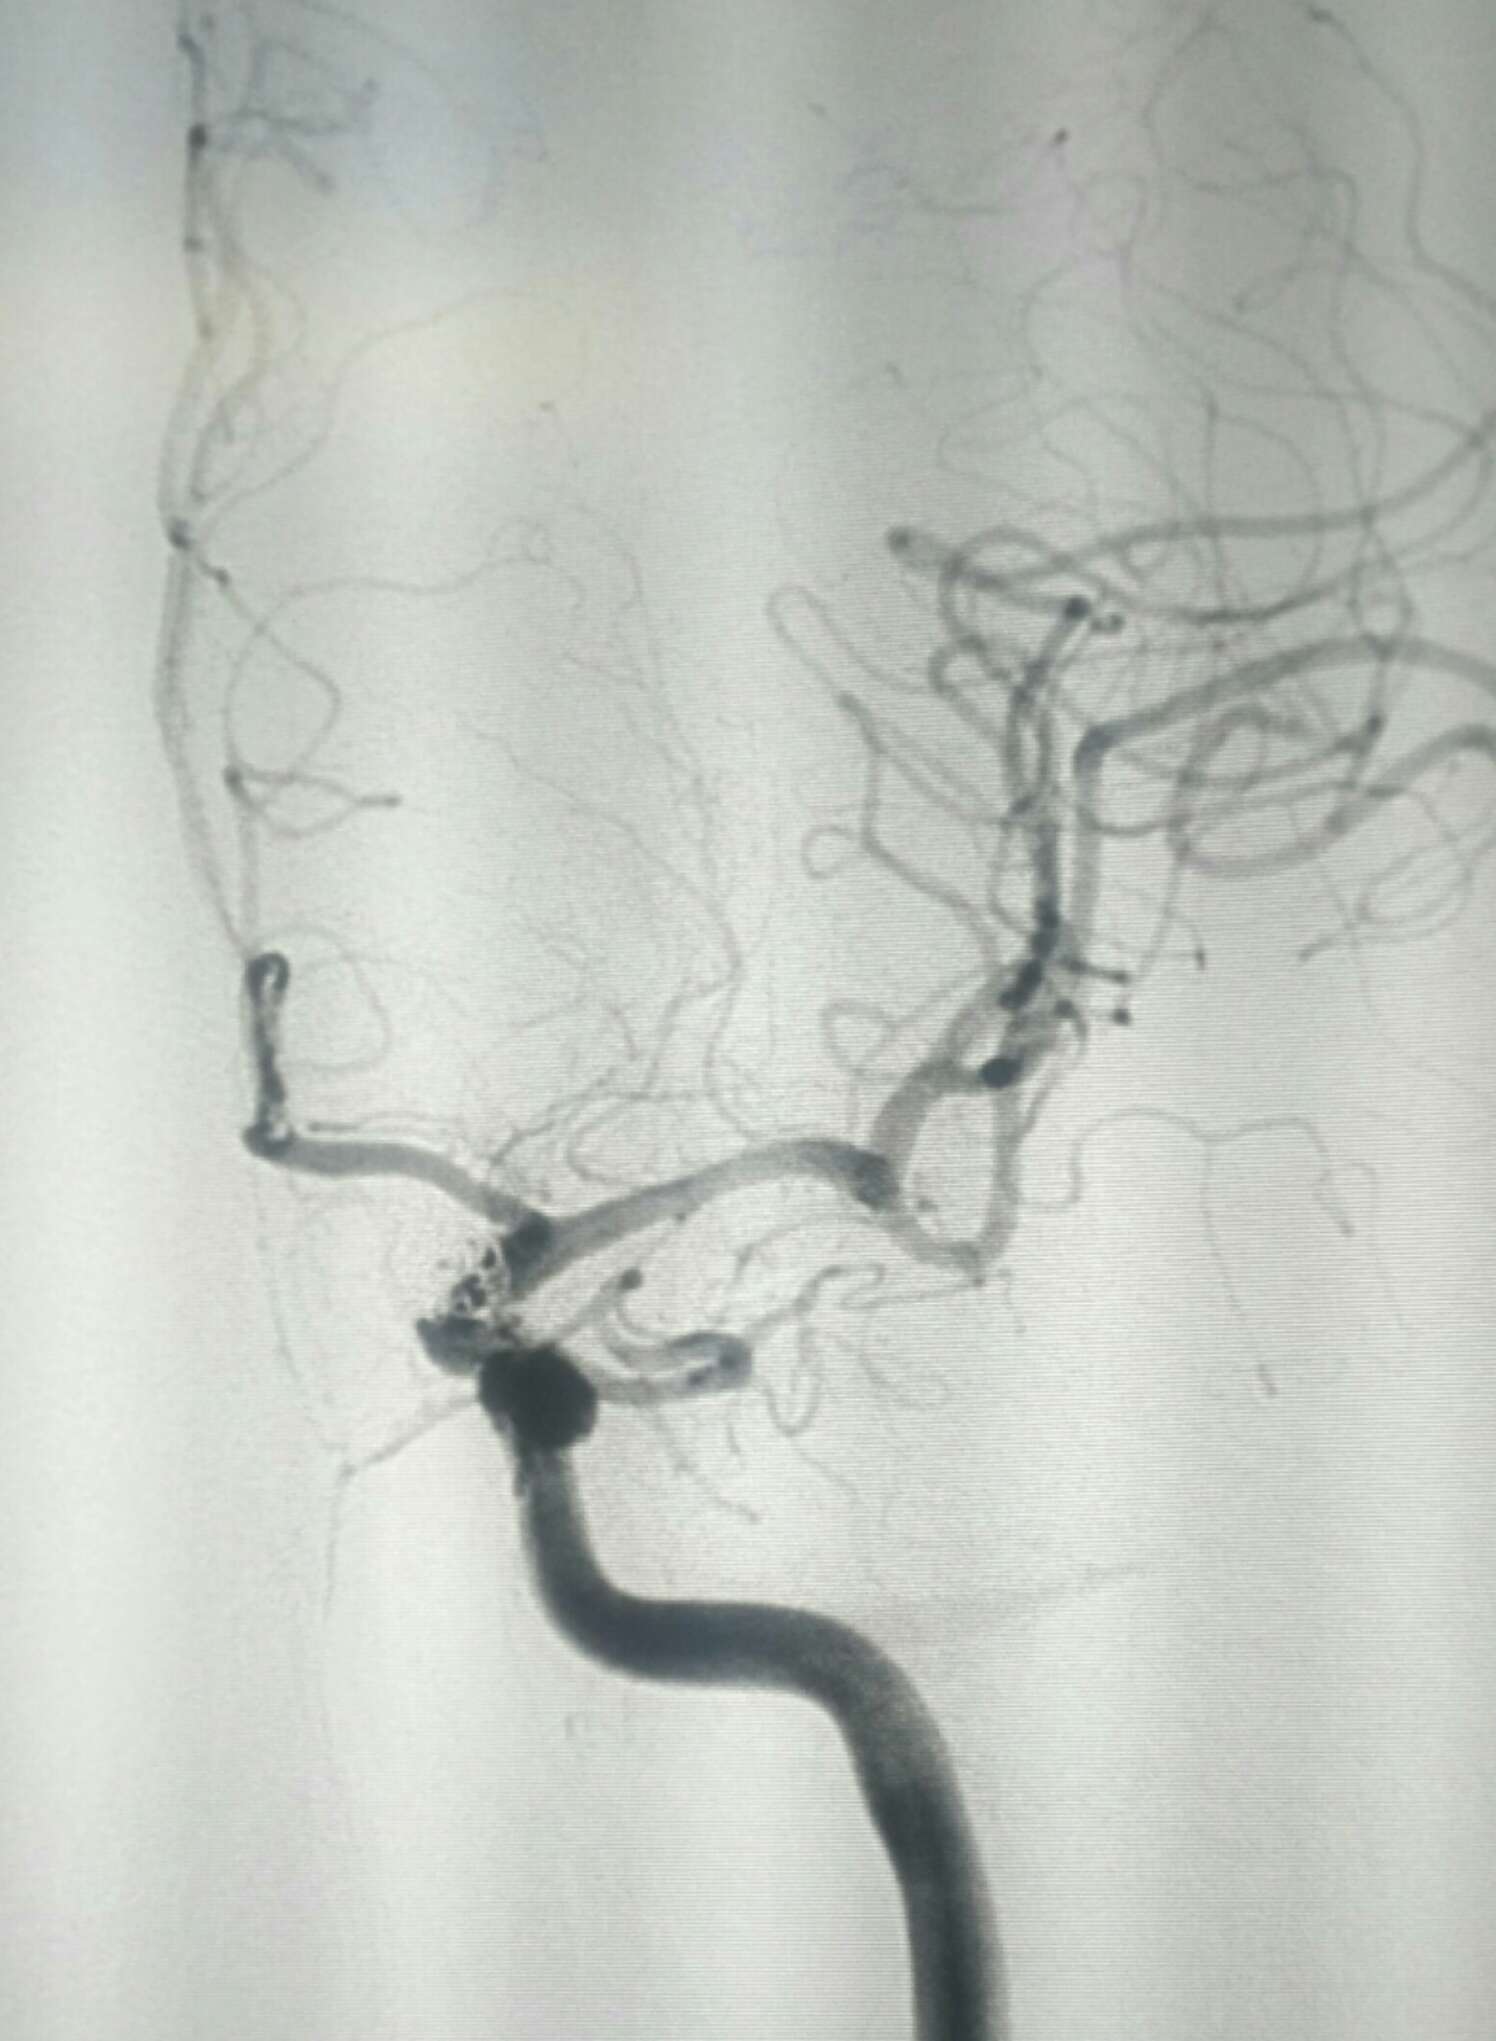

术后20天复查造影动脉瘤栓塞良好无复发显影。目前四肢活动正常,不完全运动性失语,继续康复!

侧位

显示支架

复查3D